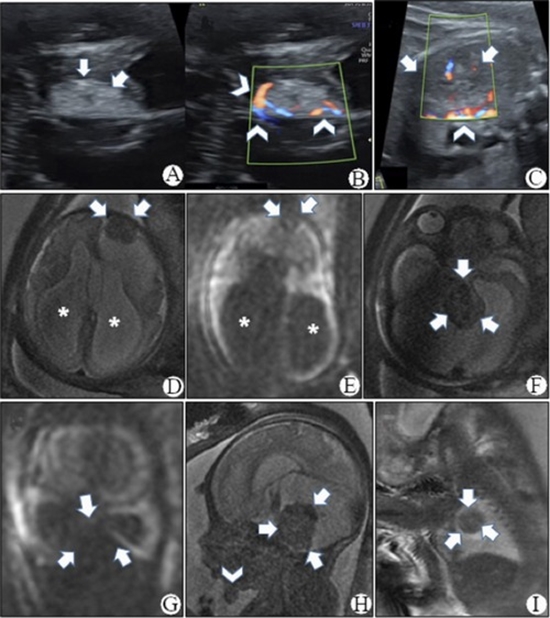

Congenital disseminated pyogenic granuloma (CDPG) is characterized by eruptive disseminated or localized lesions, which may arise spontaneously or secondary to predisposing factors. Even rarer is the occurrence of CDPG with numerous lesions affecting variable organs, which develop during the fetal period. This report describes the case of a 32-week-old fetus presenting with severe hydrocephalus and vascular intracranial and right lung masses on magnetic resonance imaging. Preterm labor occurred at the 32nd week due to preterm premature rupture of membranes, and the newborn died due to cardiac dysfunction within 2 hours postpartum. The subsequent autopsy revealed multiple violaceous to dark red papules, nodules, pedunculated and un-pedunculated mucocutaneous masses, as well as two brain lesions, a lung lesion, a thoracic wall intramuscular mass, and a pyloric mass. Microscopic examination and immunohistochemical evaluation for glucose transporter 1 (GLUT1) confirmed the diagnosis of CDPG. CDPG represents a rare condition with an elusive etiology and limited reports in the literature. Differential diagnosis from multifocal infantile hemangioma, based on GLUT1 negativity of CDPG, is imperative due to differing clinical course and treatment modalities. This report underscores a severe case of CDPG characterized by preterm labor and demise shortly after delivery, notable for its extensive involvement across multiple organs, including the brain, lung, intestine, musculoskeletal system, mucosal, and numerous cutaneous sites.